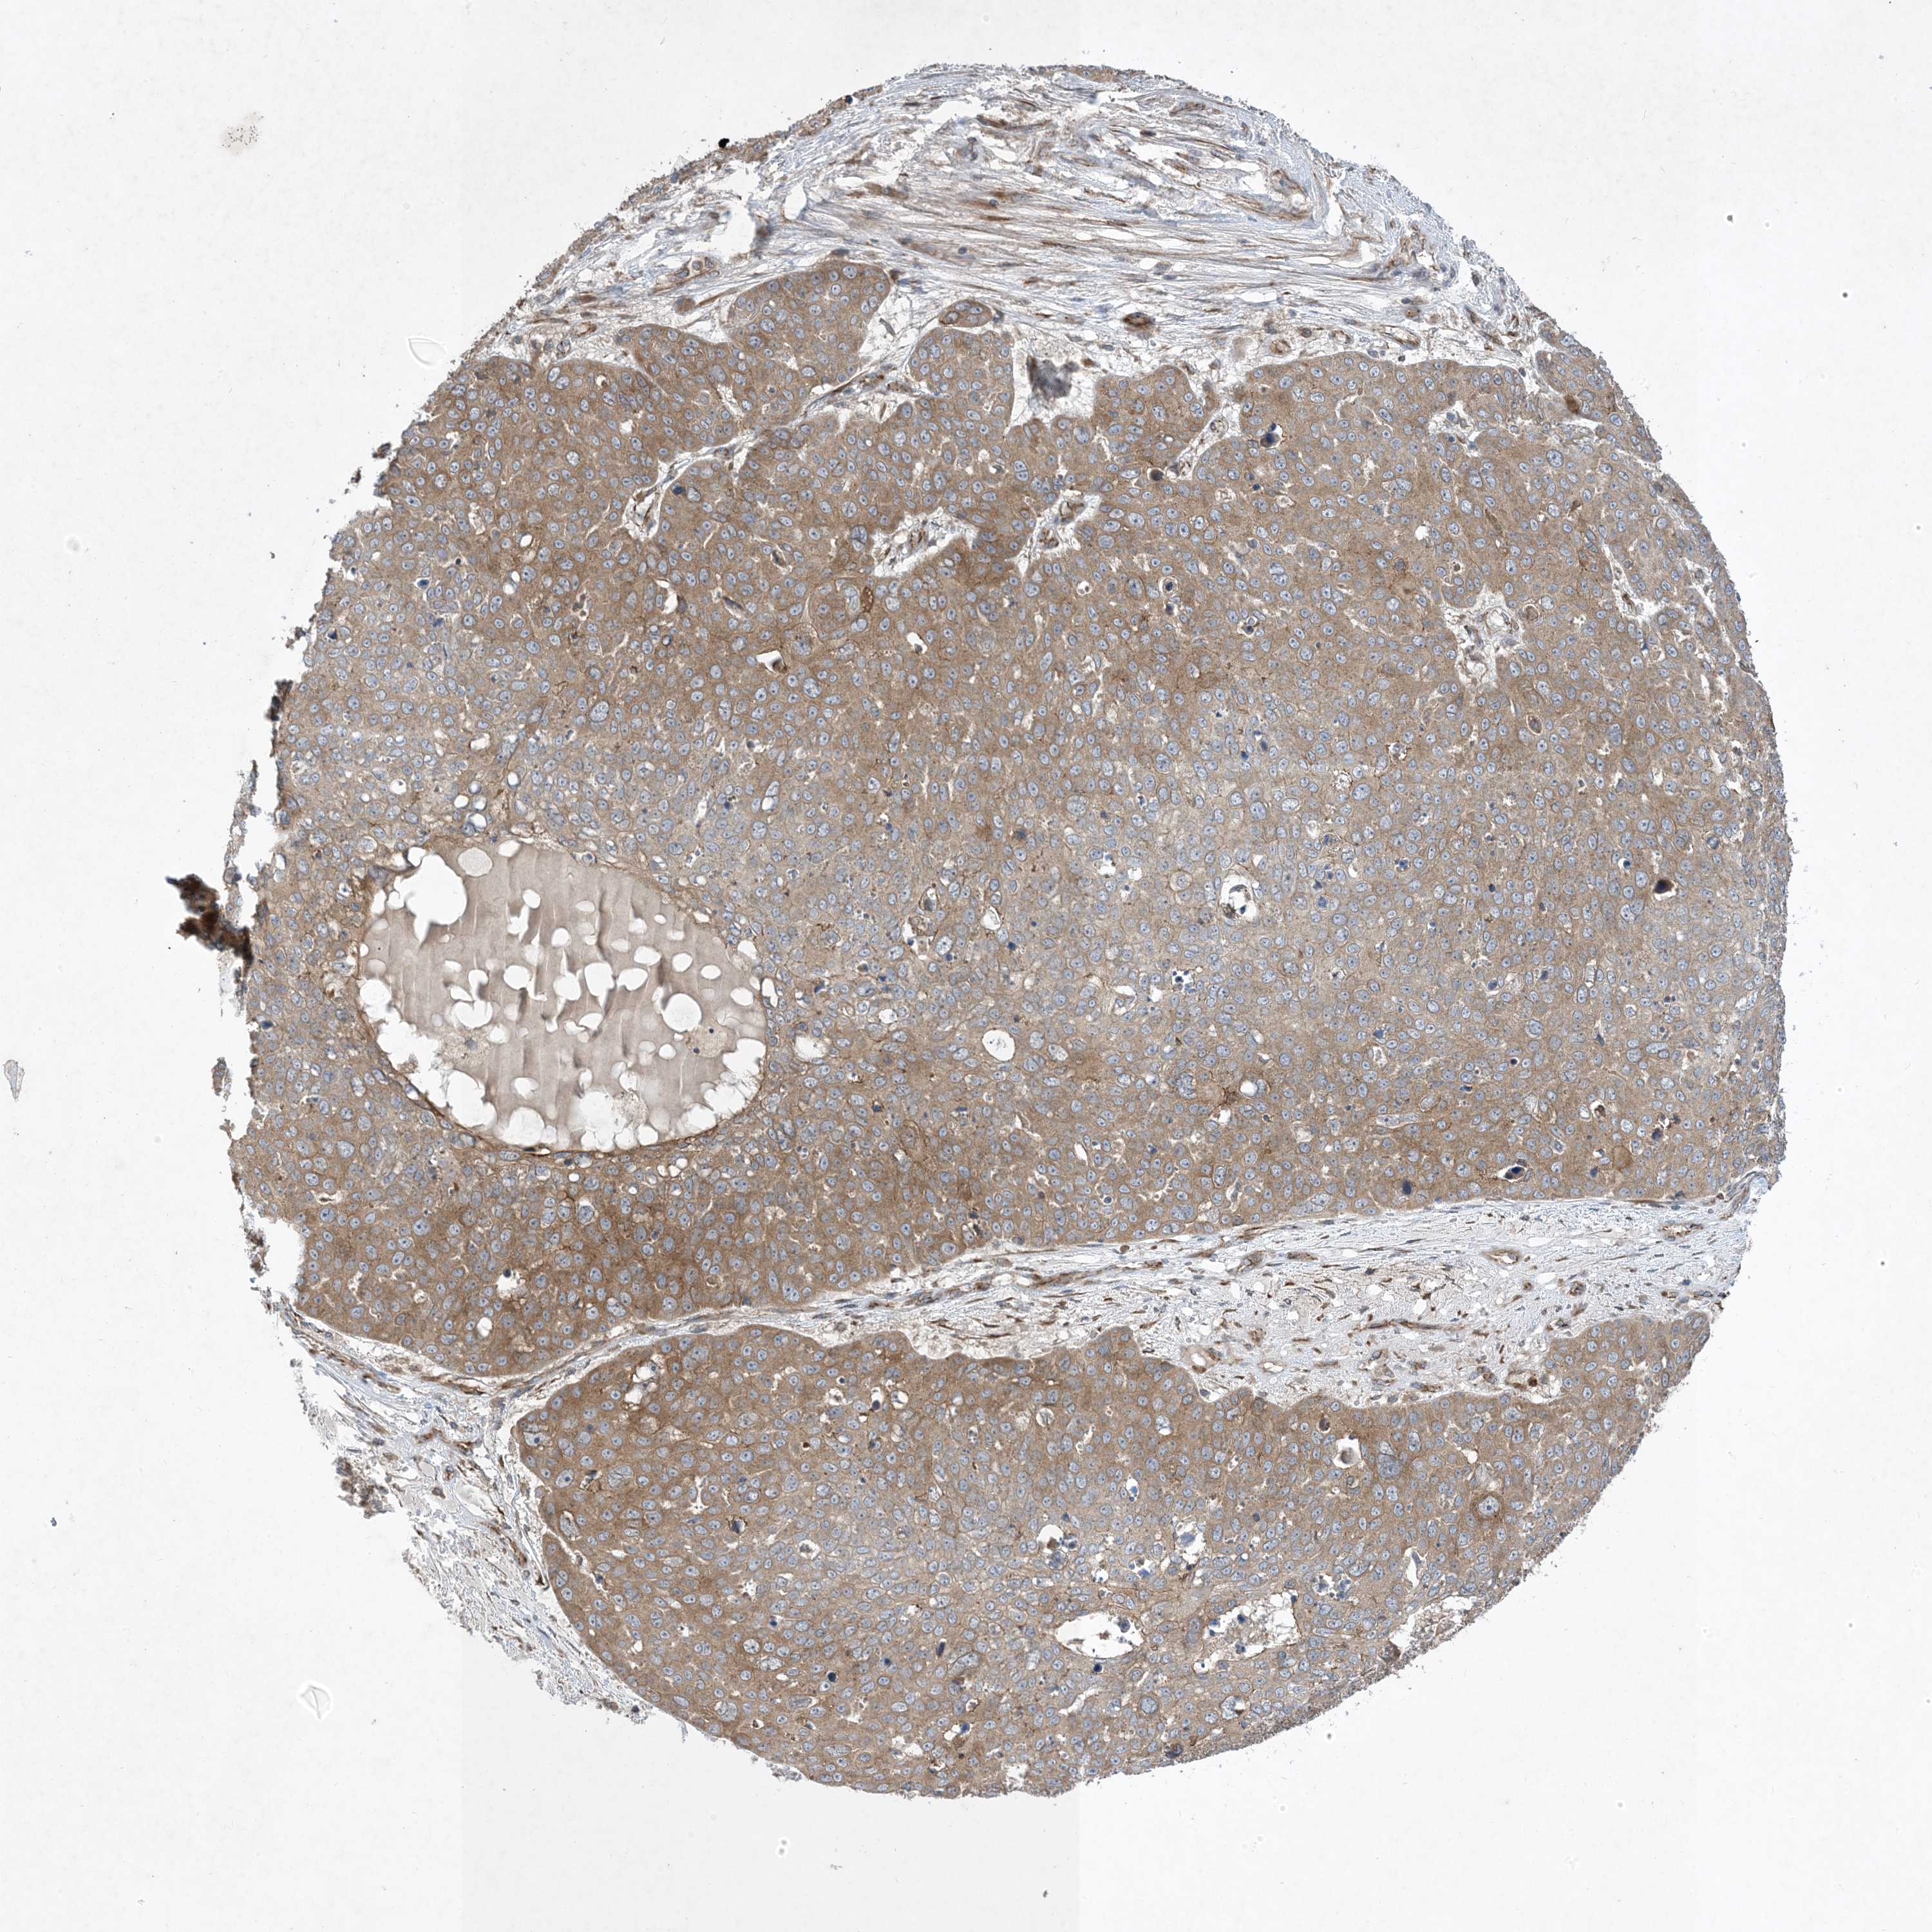

Basal cell and squamous cell cancer

SKIN CANCER - Protein expressioni

A mouse-over function shows sample information and annotation data. Click on an image to view it in a full screen mode. Samples can be filtered based on level of antibody staining by selecting one or several of the following categories: high, medium, low and not detected. The assay and annotation is described here.

Antibody stainingi

Antibody staining in the annotated cell types in the current human tissue is reported as not detected, low, medium, or high, based on conventional immunohistochemistry profiling in selected tissues. This score is based on the combination of the staining intensity and fraction of stained cells.

Each image is clickable and will lead to virtual microscopy that enables deeper exploration of all samples and also displays staining intensity scores, fraction scores and subcellular localization as well as patient and tissue information for each sample.

Antibody HPA035599

Staining

Medium

Intensity

Moderate

Quantity

75%-25%

Location

Cytoplasmic/membranous

Squamous cell carcinoma, metastatic, NOS